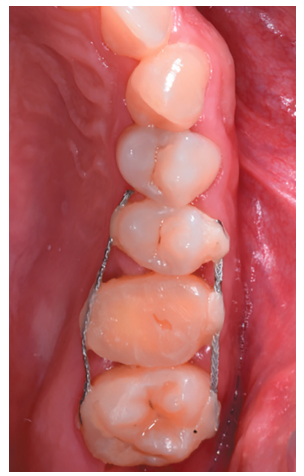

Caso clínico: se presenta el caso de un varón de 28 años, que acudió a consulta por la presencia de unos restos radiculares en localización de primer molar superior izquierdo. Se realizó un autotrasplante dental, siendo el diente donante el tercer molar superior izquierdo, que se trasplantó al alveolo del primer molar, mostrando buena evolución clínica y radiográfi ca.

Clinical case: a clinical case of a 28-yearold man is presented, who went to dental clinic for removal of left fi rst molar roots. An autotransplant was performed using left third molar as donor tooth, which was transplanted into fi rst molar alveolus, showing promising clinical and radiographic evolution.